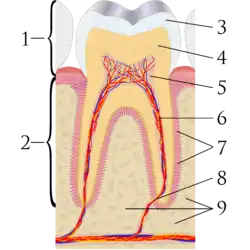

Ка́риес (лат. Caries dentium) — патологический процесс, начинающийся после прорезывания зубов, сопровождающийся деминерализацией и протеолизом, с образованием полости под действием эндо- и экзогенных факторов. Кариес — очень распространённое заболевание. В детском возрасте оно занимает первое место среди хронических заболеваний и встречается в 5-8 раз чаще, чем заболевание, занимающее второе место по распространённости, — бронхиальная астма. В США по данным разных авторов от 80 до 90 % детей с молочным прикусом, около 80 % подростков на момент окончания школы имеют кариозные полости, а 95-98 % взрослых имеют запломбированные зубы[8] .

Статистические данные показывают, что в экваториальных регионах (Африка, Азия) кариес менее распространён, чем в приполярных областях (Скандинавия, Северная Америка). В развивающихся странах также отмечен более высокий уровень распространения кариеса[9]. Следы кариеса находили у людей, живших 5 тыс. лет назад[10]. В настоящее время возникновение кариеса зубов связывают с локальным изменением pH на поверхности зуба под зубным налётом вследствие брожения (гликолиза) углеводов, осуществляемого микроорганизмами, и образования органических кислот. Частота, с которой зуб подвергается кариесогенному воздействию кислот, влияет на вероятность возникновения кариеса. После каждого приёма пищи, которая содержит сахар, микроорганизмы начинают продуцировать кислоты, которые разрушают эмаль. Со временем эти кислоты нейтрализуются буферными свойствами слюны и частично деминерализованной эмали. После каждого периода воздействия кислот на эмаль зуба неорганические минеральные составляющие зубной эмали растворяются и могут оставаться растворёнными 2 часа (см. Эмаль зуба). Если принимать углеводы периодически в течение дня, то pH в течение длительного времени будет низким, буферные свойства слюны не успевают восстановить pH, и возникает вероятность необратимого разрушения поверхности эмали.

Пульпи́т — воспаление сосудисто-нервного пучка зуба (пульпы). Наиболее часто пульпит является осложнением кариеса, а также может быть следствием ошибочных действий при препарировании зуба под ортопедические конструкции, некачественных пломб, оперативных вмешательств на пародонте, воздействия химических веществ). Также описаны случаи ретроградного пульпита (то есть инфицирование через апикальное отверстие). Пульпиты подразделяются на острые и хронические. Под острым пульпитом понимают состояние, когда инфекция проникла в пульпу при закрытой пульпарной камере (через тонкую стенку разрушенного кариесом зуба). Хронические пульпиты чаще всего являются исходом острого. Хронические пульпиты подразделяются на фиброзные, гипертрофические и гангренозные. Основная форма хронического пульпита — фиброзный пульпит, при котором происходит разрастание волокнистой соединительной ткани. Основные признаки острого пульпита — очень сильные, иррадирующие (распространяющиеся) по ветвям тройничного нерва (при остром очаговом пульпите иррадиации нет, пациент чётко может указать болезненный зуб) боли, которые усиливаются ночью. Боли носят периодический характер.

Периодонти́т — это воспаление периодонта, характеризующееся нарушением целостности связок, удерживающих зуб в альвеоле, кортикальной пластинки кости, окружающей зуб и резорбции костной ткани от незначительных размеров до образования кист больших размеров. Инфекционный периодонтит в основном является осложнением кариеса. Травматический периодонтит возникает в результате как значительного, однократного воздействия (удар при падении или попадании в лицо твёрдых тяжёлых предметов), так и вследствие незначительной, но хронической травмы (завышенная пломба, откусывание проволоки или нитки при отсутствии рядом стоящих зубов). Медикаментозный периодонтит развивается чаще всего при неправильном лечении пульпита, когда сильнодействующие препараты попадают в периодонт (например, паста, содержащая мышьяк, формалин, фенол) или раздражающие материалы (фосфат-цемент, штифты). Основной причиной развития периодонтита у детей является инфекция, когда микроорганизмы, их токсины, биогенные амины, поступающие из воспалённой некротизированной пульпы, распространяются в периодонт.